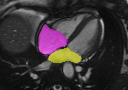

Multi-view segmentation.

The competence of our model to perform end-to-end segmentation across all planes is shown in Table 2 and Fig. 3. Our model not only exhibits comparable quantitative dice scores with nnUNet (that leverages exhaustive parameters tuning) but also shows superior performance over UNETR+ in all regions for both SA/LA planes. This benefit is gained from the learned whole-heart representation. Moreover, the superior performance against SA-only and LA-only segmentation also highlights the significance of integrating multi-view CMR information for more accurate segmentation outcomes.

GTnnUNetUNETR+Ours SA/LA onlyOurs AllRefer to captionRefer to captionRefer to captionRefer to captionRefer to captionRefer to captionRefer to captionRefer to captionRefer to captionRefer to captionRefer to captionRefer to captionRefer to captionRefer to captionRefer to caption

Figure 3: Qualitative segmentation results among nnUNet, UNETR+, and the proposed methods. UNETR+ and the proposed approach in the last column (Ours All) use all sparse CMR sequences as network input, while nnUNet and the second last column (Ours SA/LA) are trained solely with either SA or LA views.